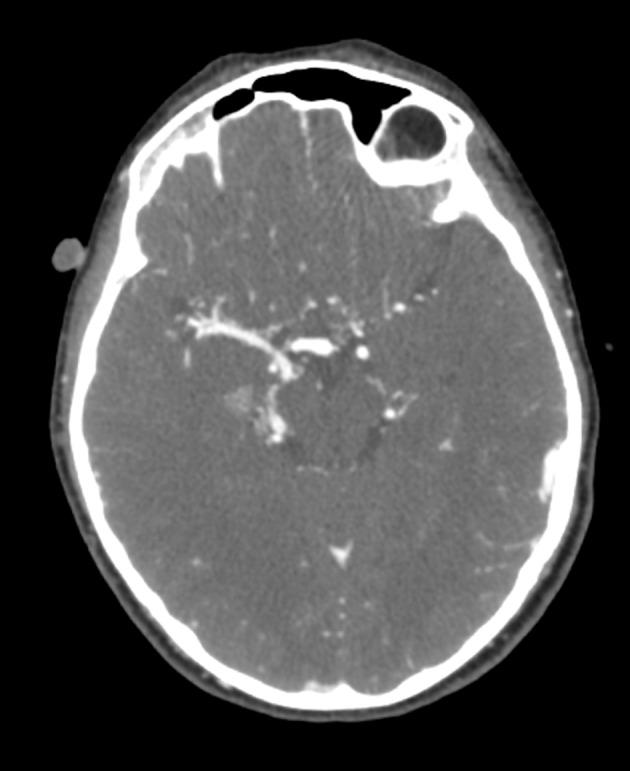

A 10-year-old male patient presented with vomiting, headache, lethargy, muscular weakness, and eye redness. The patient was mentally retarded, his right pupil was hyperemic, and he had muscle weakness on his left side. In addition, his blood pressure was high. The patient's history included a diagnosis of Moyamoya. A neck and cranial computed tomography (CT) angiography showed no flow bilaterally past the bifurcation of the carotid artery. The patient's bilateral internal carotid arteries were determined to be occluded. It was considered that his eye findings could be compatible with a metabolic disease. On metabolic screening, the patient's homocysteine level was very high. In addition, a heterozygous A1298C mutation was identified in MTHFR. Therefore, the patient was started on a diet free from homocysteine and methionine. In addition, his treatment regimen included vitamins B12 and B6. With these treatments, the patient's complications regressed.

一名10岁男性患者出现呕吐、头痛、嗜睡、肌肉无力和眼红症状。该患者智力发育迟缓,右瞳孔充血,左侧肌肉无力。此外,他血压偏高。该患者既往诊断为烟雾病。颈部和头颅计算机断层扫描(CT)血管造影显示双侧颈动脉分叉处无血流通过。确定该患者双侧颈内动脉闭塞。认为他的眼部表现可能与代谢性疾病相符。代谢筛查显示,该患者的同型半胱氨酸水平非常高。此外,在亚甲基四氢叶酸还原酶(MTHFR)中发现了杂合子A1298C突变。因此,该患者开始食用不含同型半胱氨酸和甲硫氨酸的饮食。此外,他的治疗方案包括维生素B12和B6。通过这些治疗,患者的并发症得到缓解。